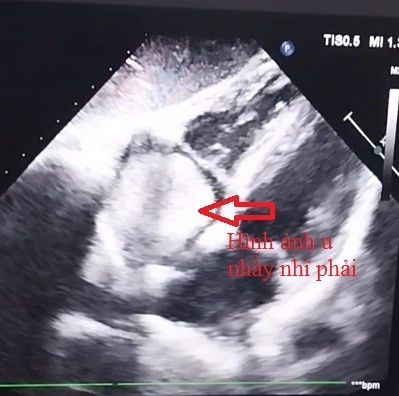

Kết quả siêu âm tim cho thấy: u nhầy nhĩ phải kích thước 39x39x52mm đồng nhất, tròn đều, có cuốn, chiếm gần trọn nhĩ phải, u rất di động. Bệnh nhân có chỉ định phẫu thuật cấp cứu. Mổ tim là một trong những can thiệp phức tạp nhất trong điều trị tim mạch, ảnh hưởng đến tính mạng bệnh nhân.

| Hình ảnh u nhầy nhỉ phải trên siêu âm tim |